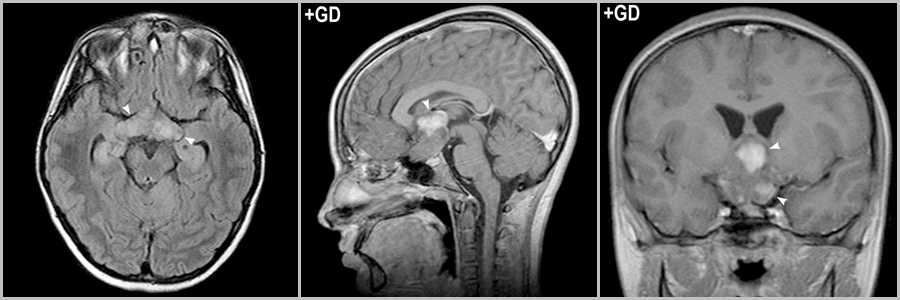

Медуллобластома

Медуллобластома предпочитает поражать мужское население (соотношение полов М:Ж — 4:1). Медуллобластома обычно наблюдаются у более молодых пациентов (пик медуллобластомы 2-6 лет), а пик пилоцитарной астроцитомы в 10-20 лет. На МРС NAA/Cho у пилоцитарной астроцитомы выше, чем у медуллобластомы. Пилоцитарная астроцитома растет из гемисферы или ножки мозжечка. Медуллобластома возникает из червя мозжечка и распространяется в полость IV желудочка, отличается более агрессивным поведением, может прорастать в дорсальные отделы моста и метастазировать по оболочкам ЦНС.

Крупное солидное образование в полости IV желудочка, раздвигающее его стенки (звёздочка на рис.13). Кистозно-солидное образование, растущее из червя мозжечка (стрелки на рис.13), интенсивно накапливающее контрастный агент (головка стрелки на рис.13).

Рис.13

Метастаз

Метастатическая опухоль менее характера для детского возраста, чем для взрослого, однако может встречаться. Метастаз, как правило, сопровождается выраженным перифокальный отеком и масс-эффектом. Скриниг легких, кожи, молочной железы, почек и желудочно-кишечного тракта поможет исключить природу вторичного генеза инфратенториального образования. При наличии других очаговых и объемных образований супратенториальной локализации диагноз метастатической опухоли более очевиден. Затруднения возникают, если метастаз солитарный и имеет кистозный компонент.

Рис.14

Крупный кистозно-солидный метастаз рака молочной железы в мозжечке (звёздочка на рис.14). Метастаз аденокарциномы лёгкого в правой гемисфере мозжечка, интенсивно накапливающего контраст (стрелка на рис.14). Метастазы в большинстве случаев множественные и могут быть обнаружены и супратенториально (головки стрелок на рис.14).